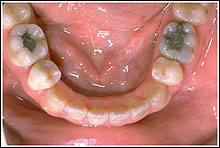

INTRAORAL PHOTOGRAPH

INTRAORAL Model